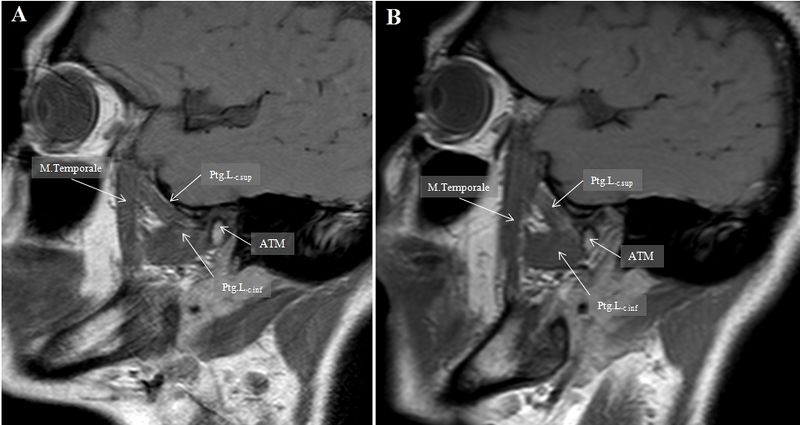

Revision as of 19:18, 15 February 2022 by Admin (talk | contribs) (==Dettagli== {{CF | Descrizione = Magnetic Resonance sagittal view of the jaw muscles<br>'' Magnetic Resonance sagittal view of the jaw muscles'' | Fonte = {{SF}} | Data = | Autore = Gianni Frisardi | Licenza = {{Cc-by-sa-4.0}} }} Category:Magnetic resonance)

| Description | Magnetic Resonance sagittal view of the jaw muscles Magnetic Resonance sagittal view of the jaw muscles | ||